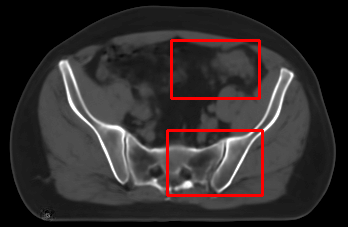

In the MRI CT translation in the Gold Atlas dataset (Fig. 8), major bones and muscles are translated faithfully. Yet, diffusion sampling leads to some inaccuracies in the outline of bones and hallucinations of the textures of inner organs. Conversely, regression sampling faithfully translates bones while still blurring the inner organs and generating artifacts. This indicates that rendering CTs is under-defined by the given MRI guidance alone.

In the quantitative analysis (Tab. 3), we found a slightly increased performance of sampling with over regression sampling in terms of PSNR and accuracy of the downstream task. As performance gains are marginal and the assessment is based on few () test cases, we still assume the performance of diffusion and regression to be similar.

Diffusion sampling YODA results in hallucinated organ shapes and textures that smoothen out and disappear when increasing the in Exp sampling or when using regression sampling. Regression sampling creates some artifacts. Note that, for all methods, the translation quality for inner organs is rather poor, whereas bone and muscle translation is reliable.

When benchmarking on the more heterogeneous and lower-quality BraTS dataset (Tab. 2, left), regression sampling of YODA achieved significantly better images than all competing methods in terms of PSNR, SSIM, and downstream glioma segmentation. Similar results were obtained in the IXI dataset (Tab. 2, right), where YODA significantly outperformed all competing methods in SSIM and PSNR. In the full-brain segmentation conducted from the synthetic images, YODA’s images were significantly better than all competing methods in at least either the Dice score or the HD. In the MRI CT task on the small pelvic dataset, regression and ExpA sampling achieved the highest SSIM, whereas the DB of Choo et al. [31] had the highest PSNR. Both, regression and ExpA sampling YODA also performed competitively in the downstream segmentation task. Note that, for all methods, the translation of inner organs was rather poor and included either texture hallucination (ResViT, I2I-Mamba, diffusion-sampling YODA) or an over-smooth image appearance (Choo et al. [31], SelfRDB, SynDiff, ExpA and regression sampling YODA, Fig. 8).